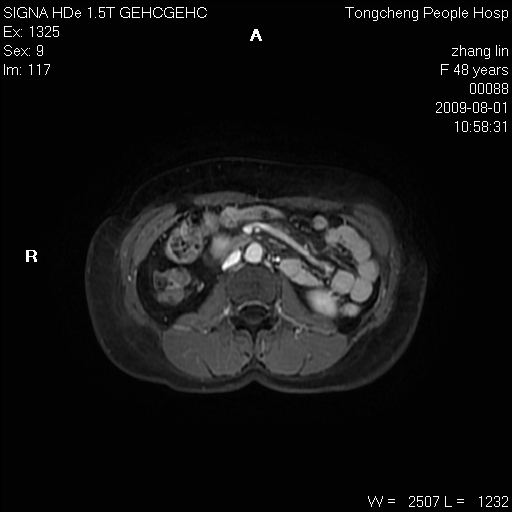

女,48岁。健康体检,彩超发现右肾占位性病变。平素健康。

临床诊断:右肾占位性病变,性质待定(囊肿?肿瘤?)。

上中腹部mr平扫+增强扫描,图像如下:

右肾上极见一类圆形病灶,t1wi呈等信号t2wi呈等高混杂信号,三期增强无强化,边界清---考虑囊肿出血。

同反相位均表现为等信号,病变无强化,考虑含蛋白的囊肿可能,弥散加权相或许有些帮助,

肝囊肿

慢性胆囊炎